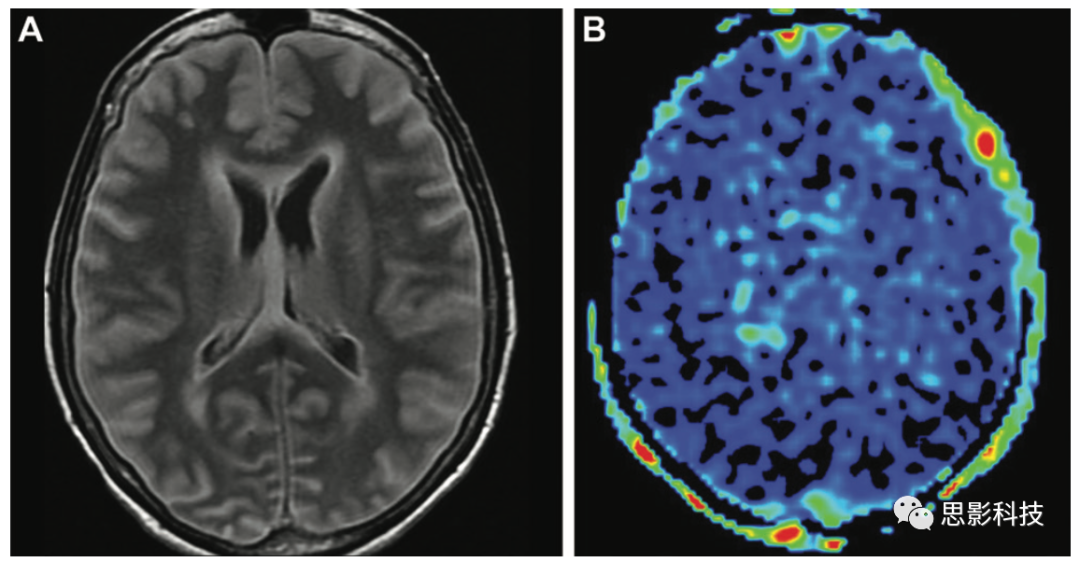

12 一例40歲女性高級(jí)別膠質(zhì)瘤,右側(cè)偏癱15天。(AB)軸位FLAIR圖像(A)顯示左側(cè)額葉病變(箭頭),ASL(B)顯示高信號(hào)(箭頭)。(C)3個(gè)月后獲得的軸位增強(qiáng)后T1加權(quán)像顯示較大的壞死性病變(箭頭),周圍有不規(guī)則強(qiáng)化,與膠質(zhì)母細(xì)胞瘤相關(guān)。